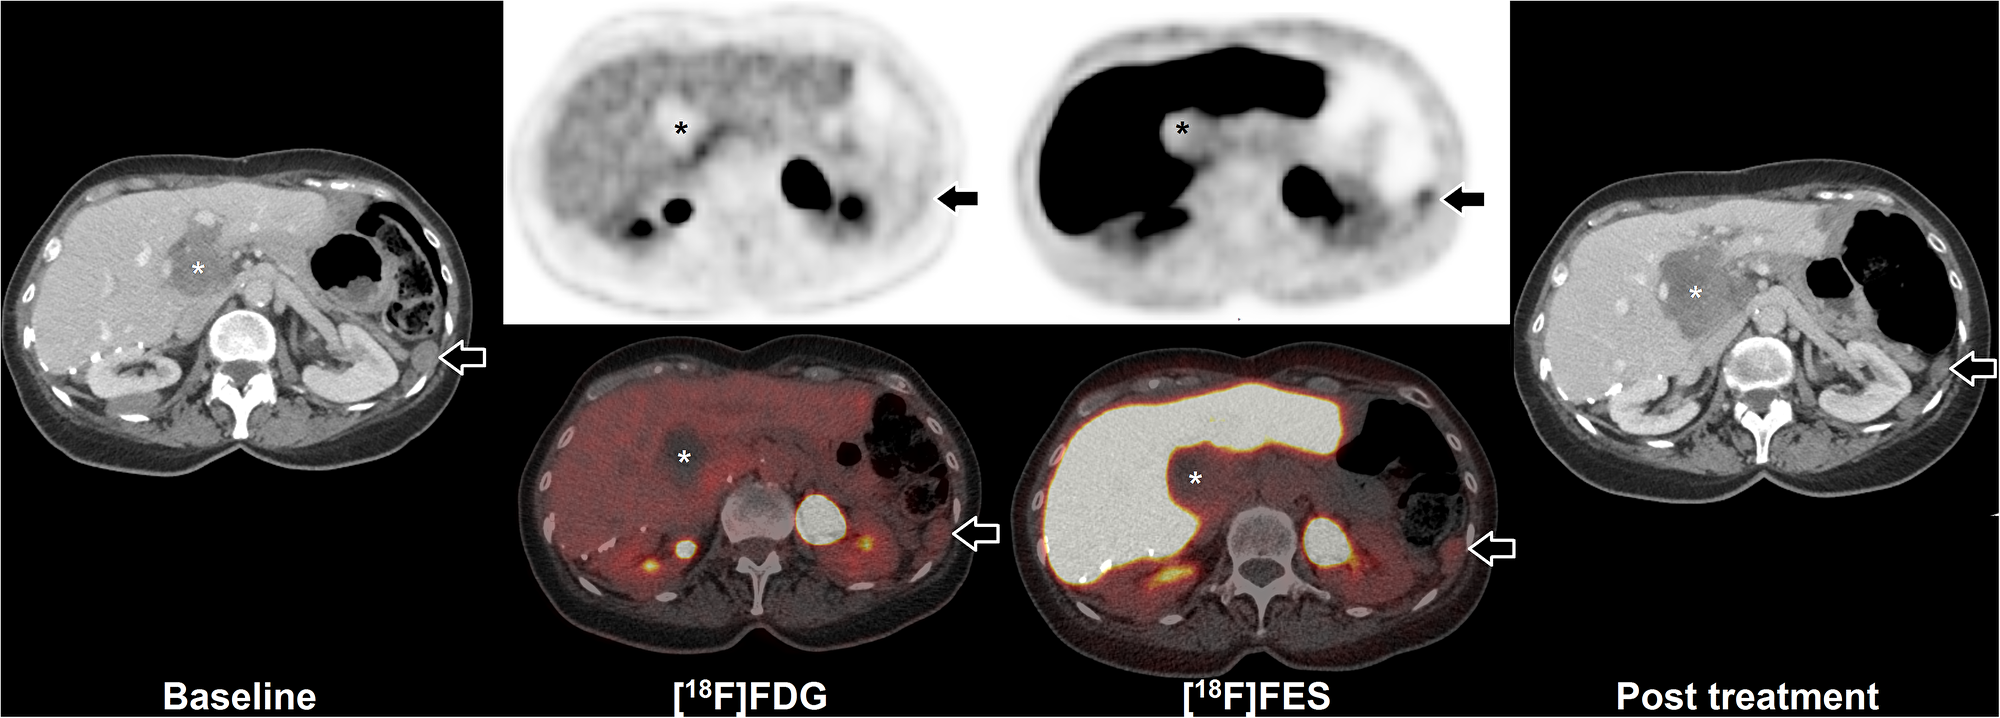

Four patients received FES-PET/CT to assess FES tumor uptake prior to anti-hormonal treatment, of which one had multiple FES positive lesions (Table 1). This patient underwent both FDG and FES-PET/CT imaging prior to anti-hormonal treatment. PET/CT showed low FDG uptake and moderate FES uptake of a peritoneal tumor lesion (Figure 2). After anti-hormonal treatment with letrozole for six months, a follow-up CECT showed progression of all FES negative lesions, whereas all FES positive lesions showed stable disease or regression (Figure 3).

Figure 2: FES-PET and response to hormone treatment. Example of FDG and FES in a 64 year old woman with peritoneal and hepatic metastases of AGCT. Baseline CECT (left) shows peritoneal disease (arrow) and hepatic disease (asterisk). Additional FDG-PET/CT shows low uptake in the peritoneal disease, whilst FES shows moderate uptake (arrows). The majority of liver hilum lesion accumulates neither FDG nor FES (asterisks). After initiation of hormonal treatment with letrozole for six months, follow-up CECT (right) showed partial regression of the FES positive peritoneal lesion (from 23 mm to 17 mm maximal diameter; arrows), whilst the FES negative hepatic lesion showed progression (from 50 mm to 65 mm maximal diameter; asterisks).